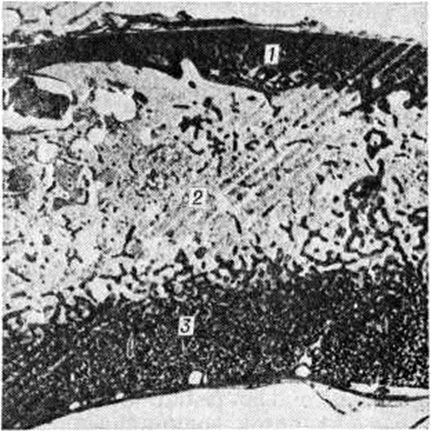

Педжета болезньПеджета болезнь (J. Paget, английский хирург и патолог, 1814—1899; синонимы: деформирующий остоз, деформирующий остит, фиброзная остеодистрофия, деформирующая остеодистрофия) — заболевание скелета диспластического характера с развитием патологической перестройки, что приводит к его характерной деформации. Заболевание впервые описал Дж. Педжет в 1877 год и назвал его osteitis deformans, считая, что в его основе лежит воспалительный процесс. Современники Педжета стали называть заболевание его именем. Позднее Педжета болезнь была объединена в одну группу с болезнью Реклингхаузена (смотри полный свод знаний: Паратиреоидная остеодистрофия) в связи с некоторым сходством гисто л. данных и получила название фиброзного остита. Штенхольм (Т. Stenholm, 1924) доказал дистрофический, а не воспалительный характер процесса при этих заболеваниях и предложил новое название — фиброзная остеодистрофия. К. Шморль (1930) выделил Педжета болезнь в самостоятельную группу и назвал её деформирующей остеодистрофией. А. В. Русаков и другие исследователи считают Педжета болезнь постнатальным диспластическим процессом. Частота Педжета болезнь составляет 0,1 — 3%. Заболевание встречается во всех странах света, чаще в Австралии, США, Западной Европе, реже в Китае, Японии, странах Ближнего Востока, Индии, Африке. Мужчины болеют чаще. Иногда Педжета болезнь возникает у нескольких членов семьи. Этиология точно не определена. Существует много гипотез: воспалительная, высказанная впервые Дж. Педжетом, гипотеза о врождённом пороке биосинтеза соединительной ткани кости, эндокринная, аутоиммунная, сосудистая, неопластическая, диспластическая. Перспективной считают вирусную гипотезу, так как обнаруживают вирусоподобные включения в ядрах остеокластов поражённой кости. Патогенез. Сущность процесса при Педжета болезнь обусловлена усиленной патологический перестройкой костной ткани, которая характеризуется многократно чередующейся сменой процессов резорбции кости и её новообразования, что приводит к своеобразной микроструктуре кости, названной К. Шморлем мозаичной. Этот процесс ведёт к понижению прочности костей и деформации их под влиянием нагрузки. В основе патогенеза при Педжета болезнь лежат глубокие нарушения метаболизма костной ткани, о чем говорят изменения некоторых биохимических констант крови и мочи больных (высокая активность щелочной фосфатазы, оксипролинурия). Патологическая анатомия. Изменения могут развиваться в одной или нескольких костях скелета (монооссальиая и полиоссальная формы), но никогда не бывают генерализованными в отличие от гиперпаратиреоидной остео дистрофии. Наиболее частая локализация процесса — таз, позвоночник, череп, бедренные и большеберцовые кости. Начальные проявления болезни морфологически почти не изучены. В поздний период становится заметным утолщение, искривление, обезображивание костей, нарушение их внутренней архитектоники. При поражении черепа процесс чаще начинается с лобной кости и распространяется на теменную, теменно-височную и затылочную области. Кости лицевого черепа поражаются сравнительно редко. Заболевание характеризуется возникновением на ограниченном участке кости очага из волокнистой остеогенной ткани и простейших, слабо обызвествленных губчатых структур. Постепенное увеличение зоны поражения приводит к утолщению, спонгиозированию костей, изменению величины и формы черепа (рисунок 1). Выраженность патологический изменений у разных больных неодинакова. Поверхность поражённого отдела кости красноватая, под периостом видны множественные мелкие отверстия сосудистых каналов. Рисунок кровеносных сосудов на внутренней поверхности костей черепа сохранен. Изменённая кость достигает 3—6 сантиметров толщины. На распиле видны поля остеосклероза (смотри полный свод знаний), участки разрежения костных структур, островки кроветворной и жировой ткани. В костях черепа преобладают однородные мелкоячеистые структуры, в большем количестве располагающиеся на внутренней костной пластинке (рисунок 2). Анатомо-топографические соотношения между костями черепа постепенно нарушаются. Передняя черепная ямка, скат основания черепа уплощаются (платибазия), боковые отделы средней ямки и задняя черепная ямка прогибаются, затылочная кость оседает на заднюю дугу атланта. |

При микроскопическом исследовании в поражённых костях различают предсуществующую и новообразованную костную ткань. Предсуществующая ткань сохраняет функциональный характер архитектоники костных структур, в ней определяют специфичную для Педжета болезнь резкую мозаичность, хаотичность рисунка костных пластин, неравномерность окраски, явления аутолитического рассасывания костного вещества, наиболее выраженного по ходу сосудистых каналов (рисунок 7). В предсуществующем костном веществе нередки микропереломы. Возникновение этих изменений отражает характер перераспределения силовых нагрузок, интенсивность патологический перестройки в деформированном костном органе.

Новообразованная костная ткань лишена функциональный дифференцировки, однотипна при любой локализации процесса. Эта ткань разрастается среди предсуществующих костных структур, постепенно занимая все более значительные пространства кости. Она построена из мелких, примитивных афункциональных костных перекладин, частично сохраняющих остеоидный характер. Рисунок костных пластин неотчётливый. Количество и зрелость костных перекладин могут быть различными. Костные перекладины окружены нежно волокнистой остеогенно-потентной тканью (рисунок 8), содержащей большое количество кровеносных капилляров, вокруг которых располагаются мелкие одноядерные клетки с тёмно-базофильными ядрами и узким розоватым ободком цитоплазмы. Новообразованная костная ткань отличается признаками интенсивного костеобразования и резорбции неполноценного костного вещества — вблизи костных перекладин располагаются цепочки и скопления клеток остеобластического ряда, на поверхности костных перекладин в лакунах залегают многочисленные остеокласты.